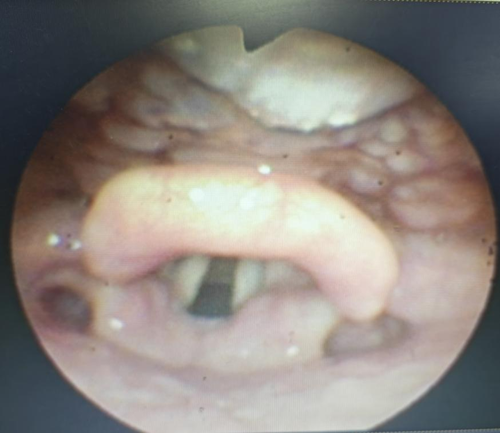

患者电子喉镜检查图(舌根、下咽、喉部大面积肿胀、溃疡合并脓性分泌物附着)

据了解,老人饮用热水后便感到咽喉剧痛,随后出现呕吐、声音嘶哑等症状,家人紧急将其送至医院。经电子喉镜检查,医生发现其咽喉部已出现广泛溃疡,伴有大量脓性分泌物;会厌肿胀明显,气道受压严重,随时可能发生窒息。加之患者高龄,合并高血压、糖尿病等基础疾病,风险极大。